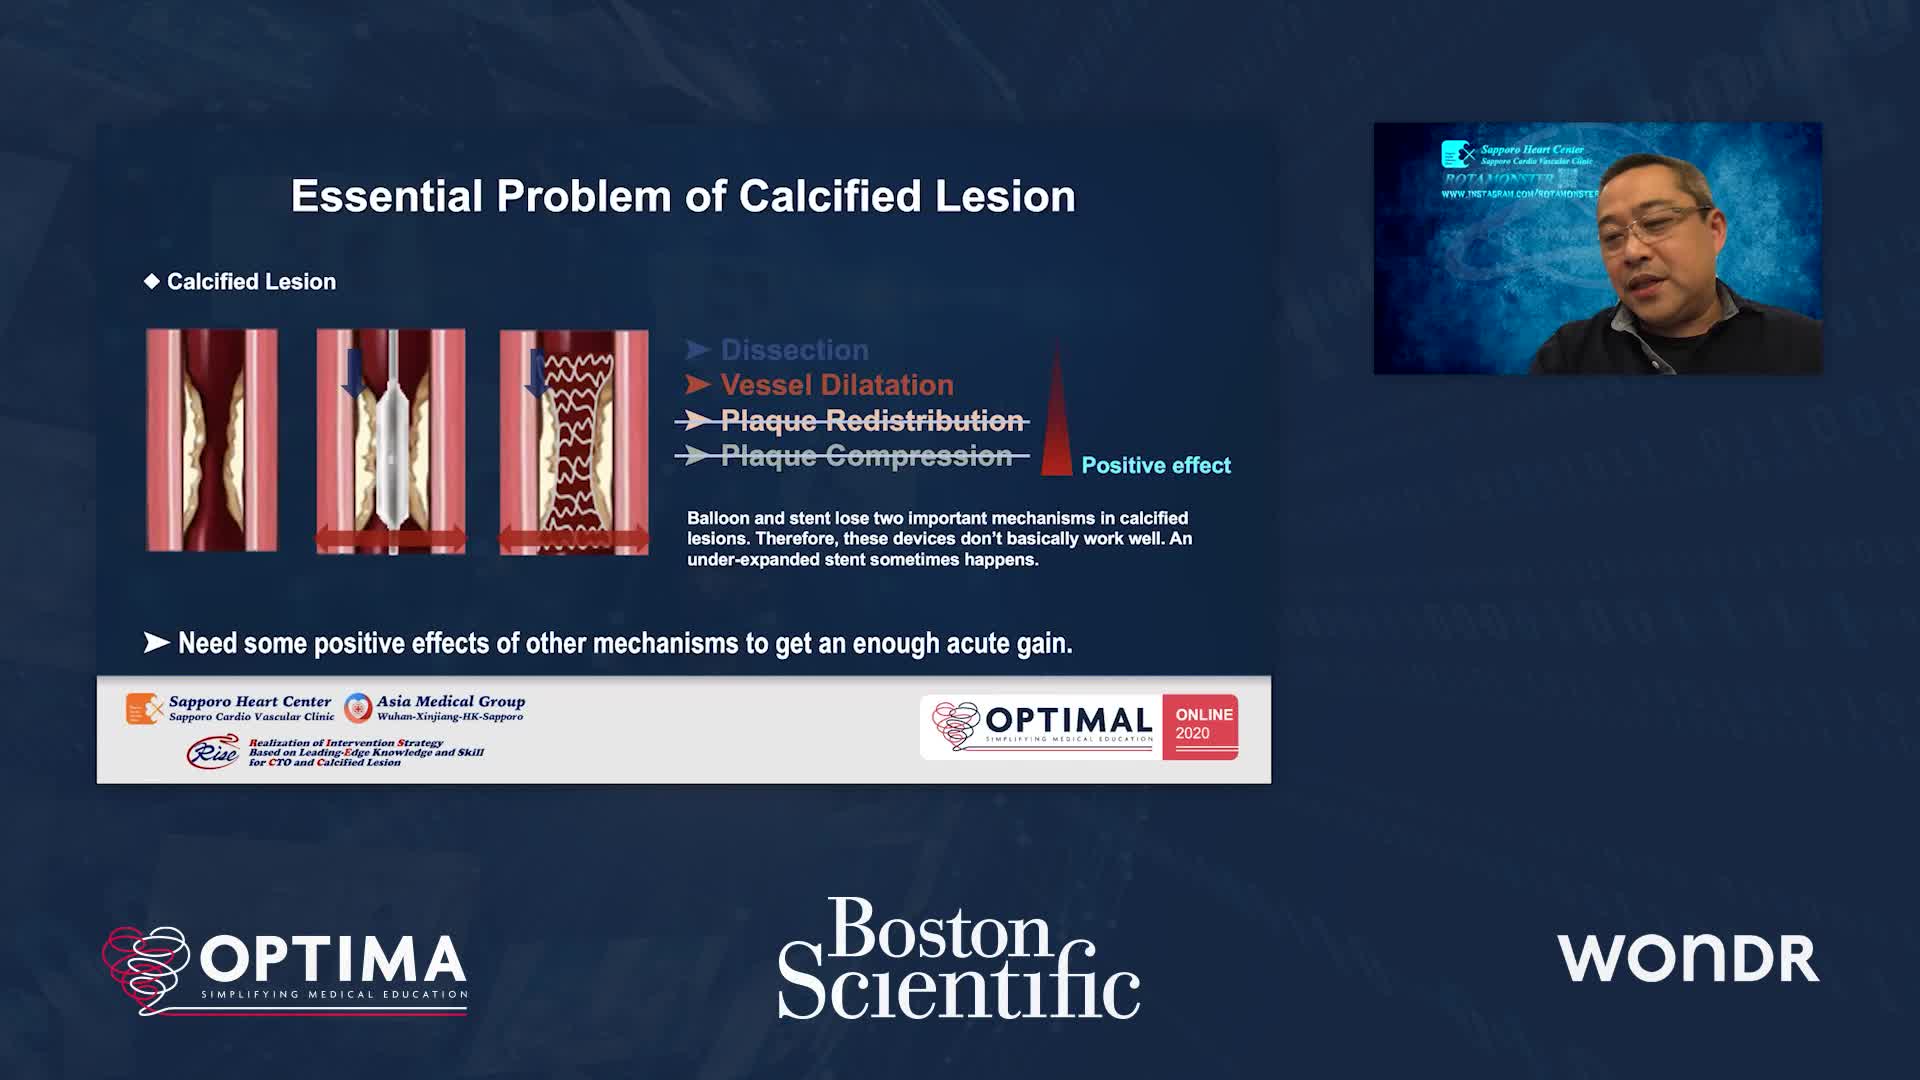

Session 2: Coronary calcium – too hard to crack?

Treatment of coronary arterial calcium (CAC) has being redefined. We explore the interaction between CAC and patient...